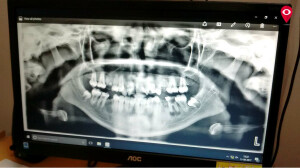

The state-of-the-art machines, devices and equipment are the need in many hospitals across the city today. Recently, two technologically advanced modern digital panoramic x-ray machines were bought at Mumbai’s Dental College and Hospital. These machines will help in diagnosing symptoms in no time and will aid the treatment.

He further added that these digital X-ray machines are worth INR 50 lakhs worth and will aid in proper diagnosis and benefit poor patients.

These machines have been kept in Department of Oral Medicine, Diagnosis and Radiology and Department of Orthodontics. Apart from these machines, a 3D workshop was also inaugurated by Girish Mahajan, Medical Education Minister.